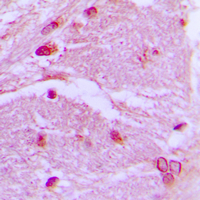

Immunohistochemical analysis of CSRP1 staining in human brain formalin fixed paraffin embedded tissue section. The section was pre-treated using heat mediated antigen retrieval with sodium citrate buffer (pH 6.0). The section was then incubated with the antibody at room temperature and detected using an HRP conjugated compact polymer system. DAB was used as the chromogen. The section was then counterstained with haematoxylin and mounted with DPX.